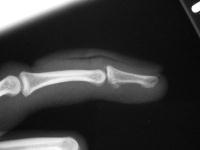

The injury:dorsal DIP fracture dislocation of the ring finger of a 16 year old male sports hopeful.

Unstable even in a well molded splint.